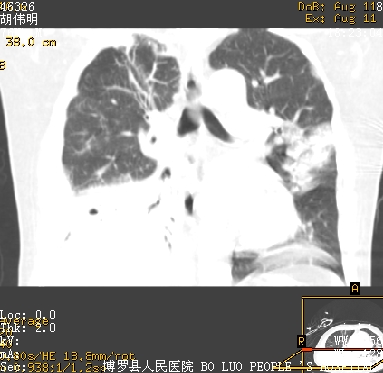

icu病人,几天都没明确诊断。m,76y,咳嗽、咳痰1周,伴气促,右胸痛入院,pe:t38.3c p135 r25 bp135/85。双肺可闻及大量湿罗音,心、腹未见明显异常。诊断:1心衰?2肺部感染?3冠心病?

11号ct

双肺感染性病变,下叶膨胀不全,胸水,左室大。

1)两肺感染性病变(右肺下叶肺脓肿可能)。2)双侧胸腔积液,以右侧为甚。

混合型肺水肿合并感染,肺膨胀不全,胸膜肥厚粘连包裹,同时肺内有陈旧性病灶。注意复查

考虑双肺感染、右肺下叶肺脓肿伴双侧胸腔积液。

ards,肺感染性病变,右下叶实变,双侧胸腔积液,右侧为著,叶间胸膜积液,右上肺陈旧性tb纤维灶,左室大。

考虑双肺感染、右肺下叶肺脓肿伴双侧胸腔积液,肺水肿。

考虑:双肺感染、右肺下叶肺脓肿,双侧胸腔积液,肺水肿.请结合临床.